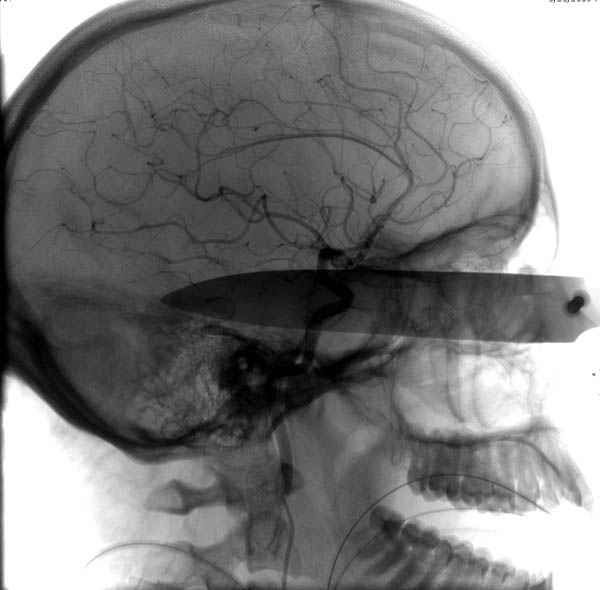

По протоколу сделаны все необходимые исследования: рентген, ангиограмма с 3Д реконструкцией, где обнаружили что все жизненно важные сосуды не задеты, даже некоторые "сидят" изгибаясь на ноже.

Одним махом нож удалить не удалось, пришлось раскачать и потом двумя руками удалили нож. Рана без кровотечения, обработана и зашита.